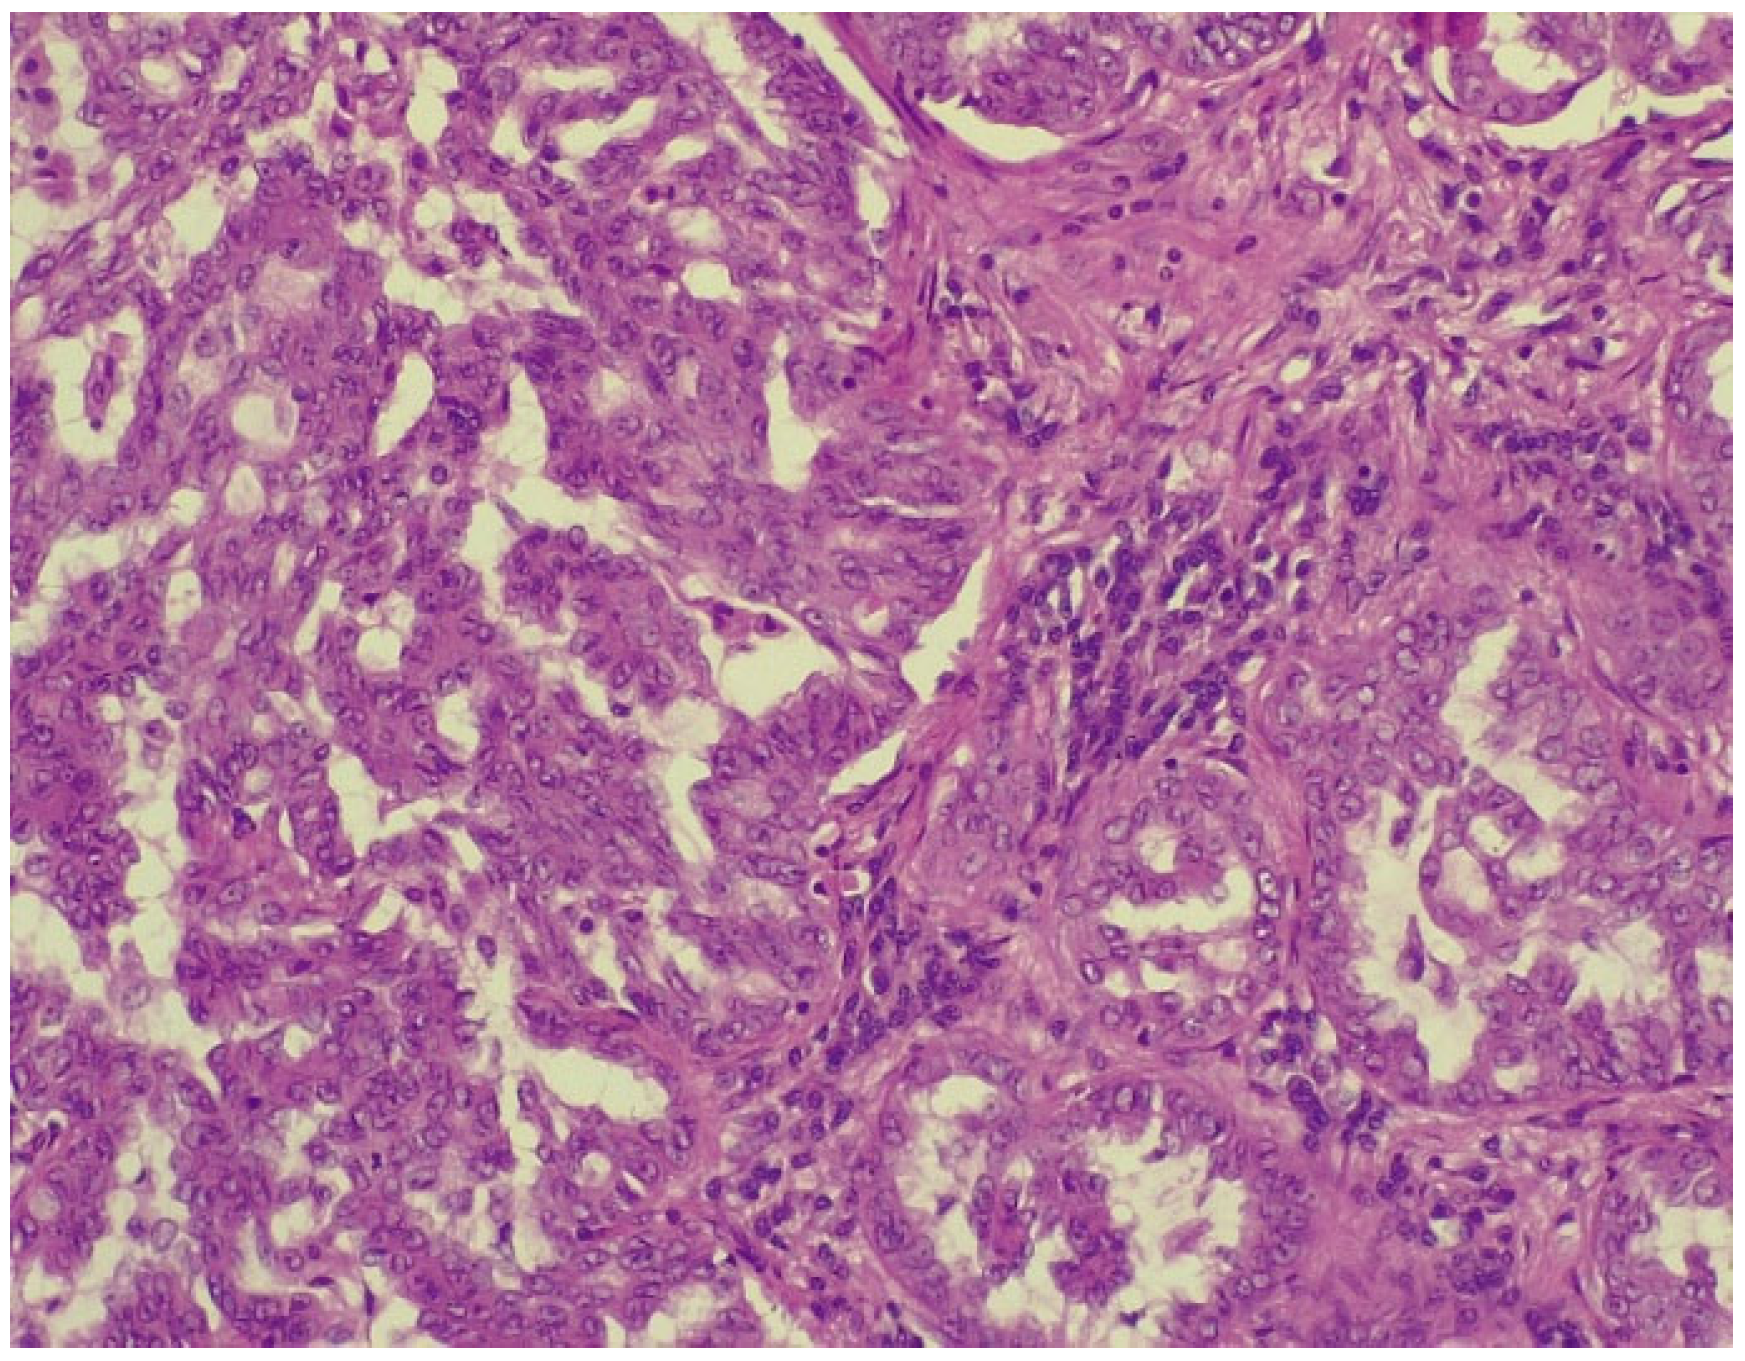

2. Case Report